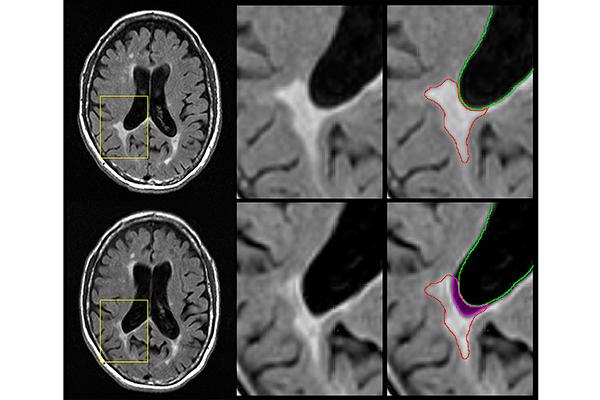

Qué significa tener hoyos negros en resultado de una resonancia?